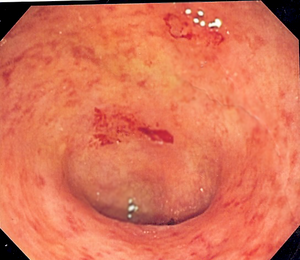

Ulcerative colitis is a long-term condition, where the colon and rectum become inflamed. The colon is the large intestine (bowel), and the rectum is the end of the bowel where stools are stored. Small ulcers can develop on the colon's lining, and can bleed and produce pus.